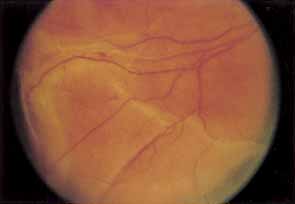

Two types of diabetic retinal detachments occur, those that are caused by traction alone (nonrhegmatogenous) (Fig. 14), and those caused by retinal break formation (rhegmatogenous) (Figs. 15 and 16). Characteristics of nonrhegmatogenous (traction) detachment in PDR include the following: (1) the detached retina is usually confined to the posterior fundus and infrequently extends more than two-thirds of the distancd to the equator, (2) it has a taut and shiny surface, (3) it is concave toward the pupil, and (4) there is no shifting of subretinal fluid.

Fig. 14 Traction retinal detachment. The detached retina has a smooth noncorrugated appearance and is convex toward the pupil.

Fig. 15 Combined traction/rhegmatogenous retinal detachment. The detached retina has a corrugated appearance and is concave toward the pupil.

Fig. 16 Round hole near fibrous proliferation.